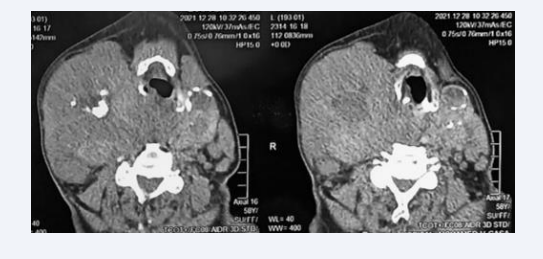

A cervicothoracic CT scan (Figure 3) showed a plunging right thyroid mass of tumoral appearance, very heterodense with several areas of necrosis, compressive and pushing the larynx and trachea to the left; another plunging left thyroid mass with micro and macro calcifications, pushing the trachea to the right; and multiple bilateral laterocervical enlarged lymph nodes of metastatic appearance.

Cervical level of cervicothoracic CT scan showing 2 plunging right and left thyroid masses associated with bilateral laterocervical  adenopathies.

Figure 3: Cervical level of cervicothoracic CT scan showing 2 plunging right and left thyroid masses associated with bilateral laterocervical adenopathies.